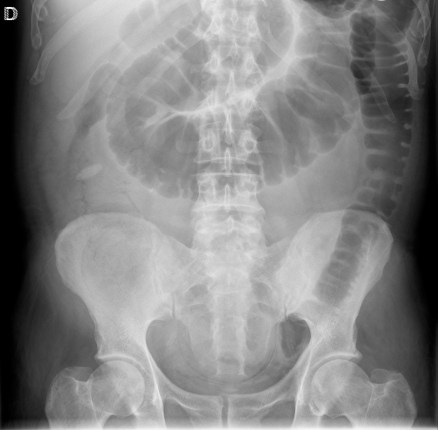

Se realiza TC de abdomen en vacío y con contraste en fase portal:

Estamos ante un cuadro de isquemia intestinal en un paciente con bajo gasto cardiaco con afectación principal de asas intestino delgado, territorio vacularizado por la arteria mesentérica superior.